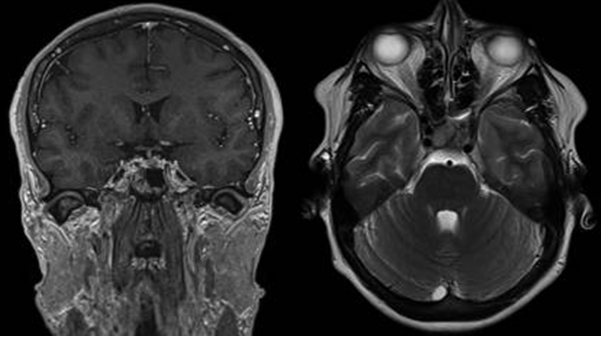

Tim 4G高密度一体化头颈线圈提供高分辨率头部成像,更多的线圈单元数支持更高的iPAT并行采集因子,有利于减少EPI序列的磁敏感伪影。

CASE 2:多发硬化 MS